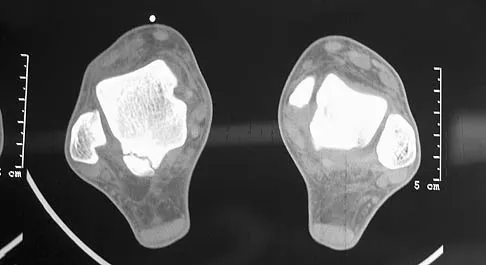

A 30-year-old man has had intermittent swelling of his right ankle for the past 6 months. He denies any history of trauma. Radiographs reveal osteolytic changes on both sides of the joint. An axial CT scan and a T2-weighted MRI scan are shown in Figures 40a and 40b. He undergoes surgical excision. An intraoperative photograph and a biopsy specimen are shown in Figures 40c and 40d. What is the most likely diagnosis?

Explanation